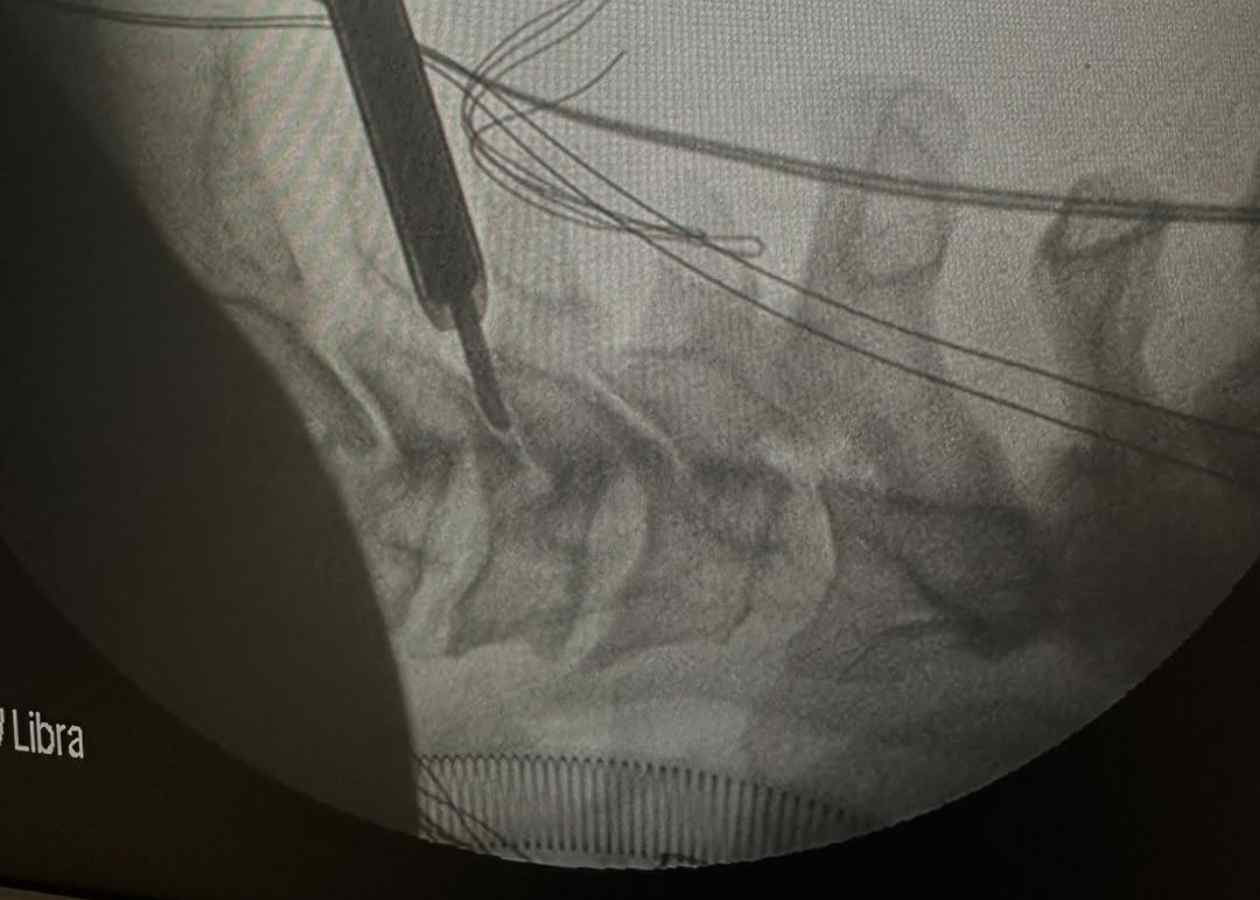

Tam Kapalı Bel Fıtığı Ameliyatı Nedir?

Tam kapalı (full endoskopik) bel fıtığı ameliyatı, küçük bir kesi üzerinden özel kamera ve mikro cerrahi ekipmanlar ile gerçekleştirilen modern bir omurga cerrahisi yöntemidir. Bu teknikte, omurgaya ulaşmak için kaslar kesilmez; kas lifleri arasından girilerek doğal doku yapısı büyük ölçüde korunur.

Kas ve bağ dokularının korunması, ameliyat sonrası ağrının daha az olmasını ve hastanın günlük yaşamına daha hızlı dönmesini sağlar. Aynı zamanda omurganın stabil yapısı bozulmadığı için iyileşme süreci daha konforlu ilerler.

Klasik açık ameliyatlara kıyasla daha az travmatik olan bu yöntem, hem cerrahi hassasiyeti artırır hem de hastaya daha güvenli ve kontrollü bir tedavi süreci sunar. Bu sayede, doğru hasta seçimi ile uygulandığında oldukça etkili sonuçlar elde edilebilir.

Ameliyat Süreci Nasıl İlerler?

Tam kapalı bel fıtığı ameliyatı genellikle şu aşamalardan oluşur:

- Hastanın ameliyat öncesi değerlendirilmesi

- Lokal veya genel anestezi uygulanması

- Küçük bir kesi ile endoskopik giriş yapılması

- Fıtıklaşmış disk dokusunun temizlenmesi

- İşlemin tamamlanması ve kısa süreli gözlem

Ameliyat süresi genellikle 45-90 dakika arasında değişmektedir. İşlem sonrasında hastalar kısa sürede ayağa kalkabilir.